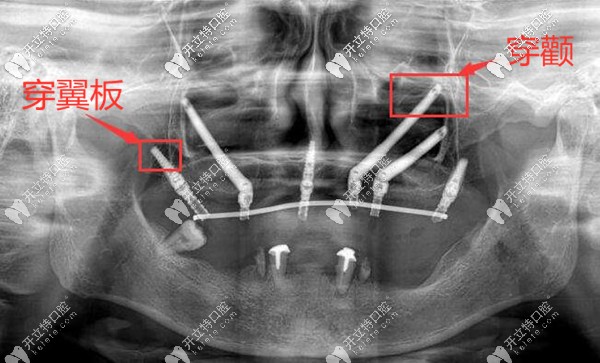

熊院長倡導微創(chuàng)、盡早修復、長久穩(wěn)定的種植理念。尤其是在上頜骨大量不足的情況下,不用做上頜竇提升、植骨手術(shù);而是采用手術(shù)中少剝離軟組織、不依賴植骨,為顧客做穿顴穿翼板這種可靠的種植手術(shù),并且還能實現(xiàn)即刻修復的種植效果。

上頜牙槽骨大量缺失,穿顴穿翼板種植案例▼

深圳正夫口腔熊靖宇穿顴穿翼板種植牙案例